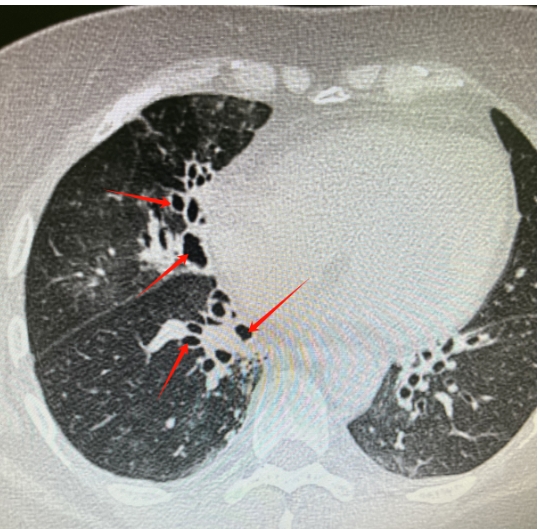

情况十分危急,肿瘤科蒋秀清主任赶来会诊。经过仔细检查和评估,蒋主任决定采用经导管介入栓塞治疗。这就好比是给 “决堤” 的血管 “堵口子”—— 通过一根细细的导管,找到出血的血管,再用特殊的材料把它堵住。

在和阿姨的家人详细沟通,征得他们同意后,医生们迅速为阿姨完善了各项检查,并马上进行了急诊手术。手术中,医生们全神贯注,精准操作,成功完成了经导管选择性支气管动脉栓塞治疗。